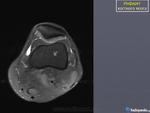

Инфаркт костного мозга.

Бывает, вот только "фейс" отличается.

На представленных рентгенограммах паттерн действительного не "инфарктный", но спорить можно долго, а правду узнаем только выполнив МРТ или РКТ.

Да, я привел иллюстрацию с radiologyassistant.nl

Да, это там это называется "bone infarction", и что? В процесс вовлекается костный мозг. Вы настаиваете на использовании термина "инфаркт кости" и отрицаете название "инфаркт костного мозга"?

Визуально процесс проявляется обызвестлением, о чем свидетельствуют и приведенные Вами же сканы.

Мое утверждение касалось принципиальной возможности обызвестления костного мозга, в частности при инфаркте. Я не настаивал и не настаиваю, что автором поста на рентгенограммах представлен инфаркт мозга/кости, а чем уже говорил.

Возможности КТ и МРТ в диагностике данного дифряда широко известны и как безвредный метод исследования можно рекомендовать МРТ нижней трети бедра.